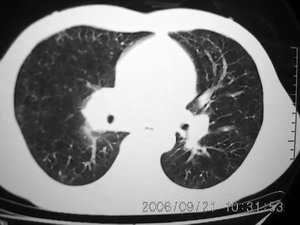

男 27岁 咳嗽一个月,治疗无效。

右肺下叶后段及右肺门附近见斑片状模糊影,密度不均,部分实变,右肺门附近见肿大淋巴结影.

两肺弥漫均匀分部粟粒壮影 右肺基底段不规则软组织密度影其内密度不均 纵隔内淋巴结钟大 请进一步右肺病灶薄层检查及补充病史后再会诊

右肺下叶后基底段结节样病灶,边界不规则,密度不均,右肺门团片影,肺门增大,纵隔见肿大淋巴结.结合临床首先考虑:肺结核.

图像显示:右下肺门增大,伴右下肺斑片状高密度影,密度不均;右下肺支气管管壁增厚,纵隔内淋巴结肿大。意见:支气管内膜结核、结节病。建议行纤支镜检查。

右下肺脊柱旁结节样肿块,可见毛刺,右侧肺门影增大,并见气管隆突前、主动脉窗内多发结节影。

临床无明显发热,男 27岁 咳嗽一个月,治疗无效。

考虑青年人周围型肺癌并右肺门、纵隔淋巴结转移。

右肺门影增大,纵隔内可见多个淋巴结肿大,右肺下叶内后基底段斑片状模糊影,两肺间质性改变;考虑右肺内结核并右肺门及纵隔淋巴结结核可能性大;职业病及结节病待排;肿瘤不太支持,年龄轻,无咯血,未见明显支气管狭窄,建议穿刺活检。